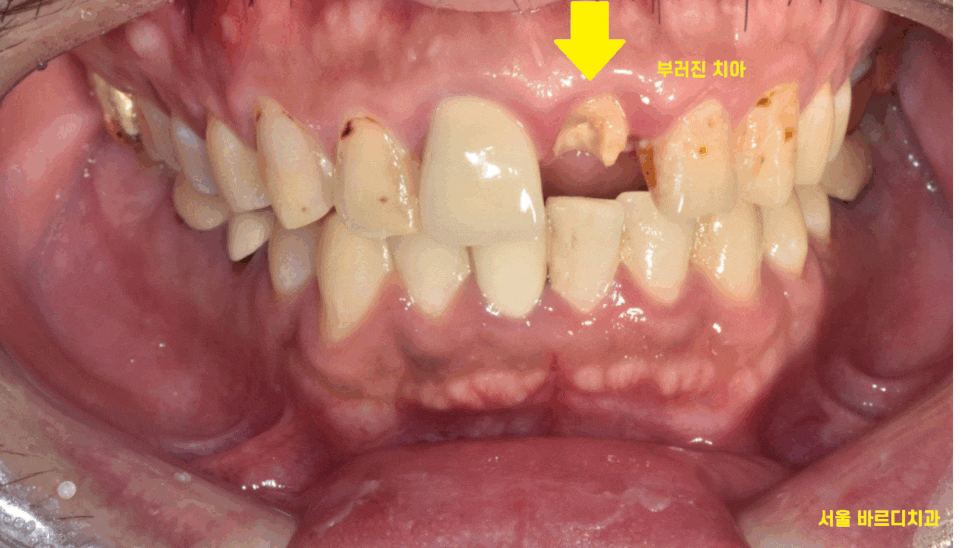

한눈에 봐도 치아가 많이 부러졌습니다.

23.12.18